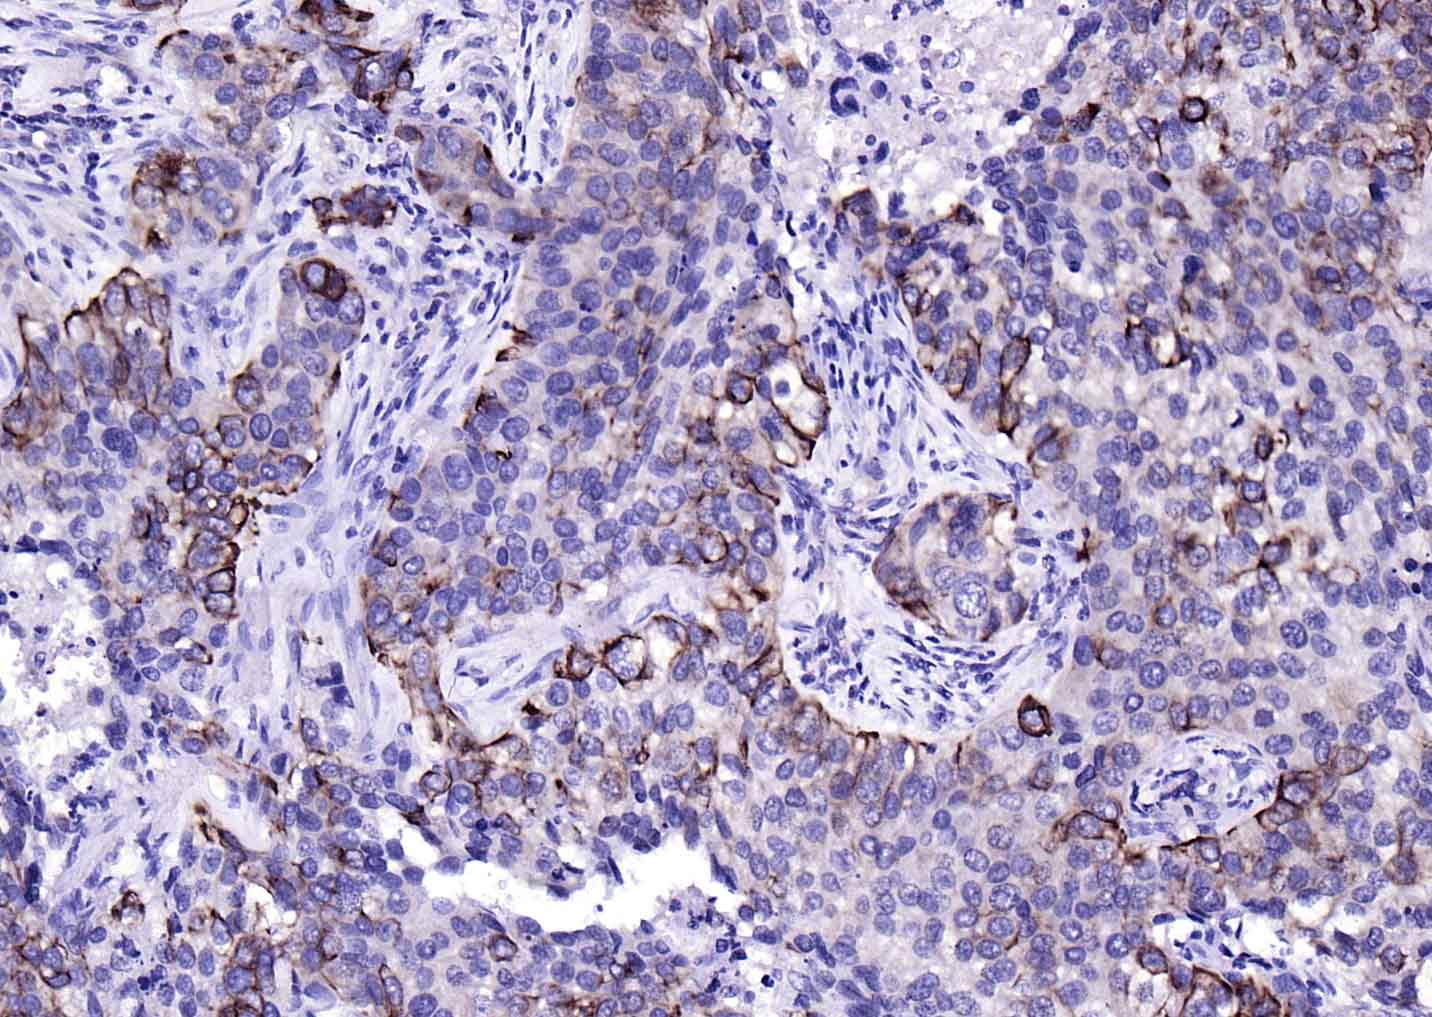

IHC-PHuman1:100-500

细胞角蛋白17单克隆抗体-bsm-33087M细胞角蛋白17单克隆抗体-bsm-33087M细胞角蛋白17单克隆抗体-bsm-33087M细胞角蛋白17单克隆抗体-bsm-33087M细胞角蛋白17单克隆抗体-bsm-33087M细胞角蛋白17单克隆抗体-bsm-33087M细胞角蛋白17单克隆抗体-bsm-33087M细胞角蛋白17单克隆抗体-bsm-33087M细胞角蛋白17单克隆抗体-bsm-33087M细胞角蛋白17单克隆抗体-bsm-33087M细胞角蛋白17单克隆抗体-bsm-33087M细胞角蛋白17单克隆抗体-bsm-33087M